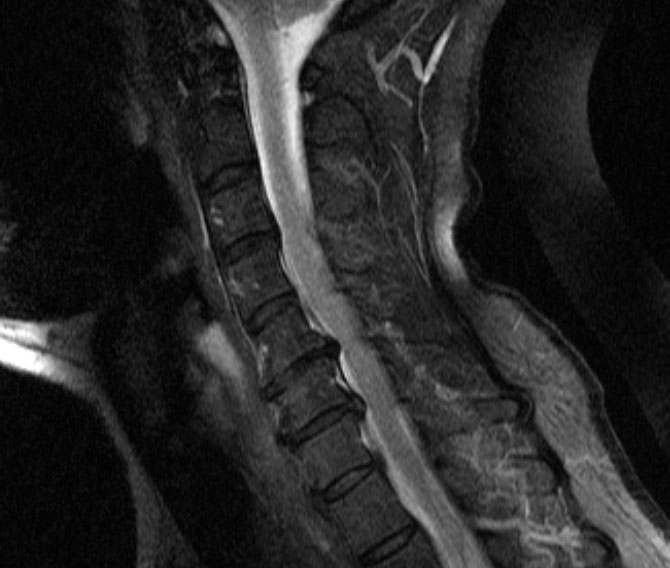

Why my neck hurt and how they fixed it: